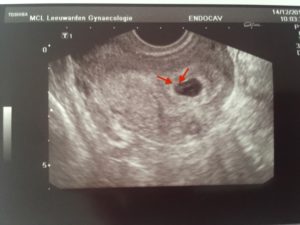

- На 21 день после переноса эмбрионов врач уже может увидеть плодное яйцо, диагностировать благополучную беременность.

- Появляется возможность заметить, сколько эмбрионов прижилось, нет ли внематочной беременности, где ребенок закрепился.

- Иногда врачи назначают ультразвуковое исследование на 6 неделе, что обусловлено жизнеспособностью плода. К сожалению, не всегда первое ЭКО заканчивается беременностью. Но с каждой новой попыткой шансы женщины растут. К 6 неделе после пересадки есть возможность отчетливо услышать, как бьется сердце плода.

Первое УЗИ после ЭКО назначают на 21 – 28 сутки после экстракорпорального оплодотворения. Это стандартная процедура диагностики, позволяющая обнаружить не только беременность, но и положение ребенка, состояние организма будущей матери.